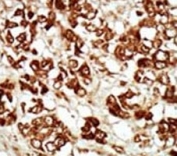

IHC analysis of FFPE human hepatocarcinoma tissue stained with the ZAK antibody